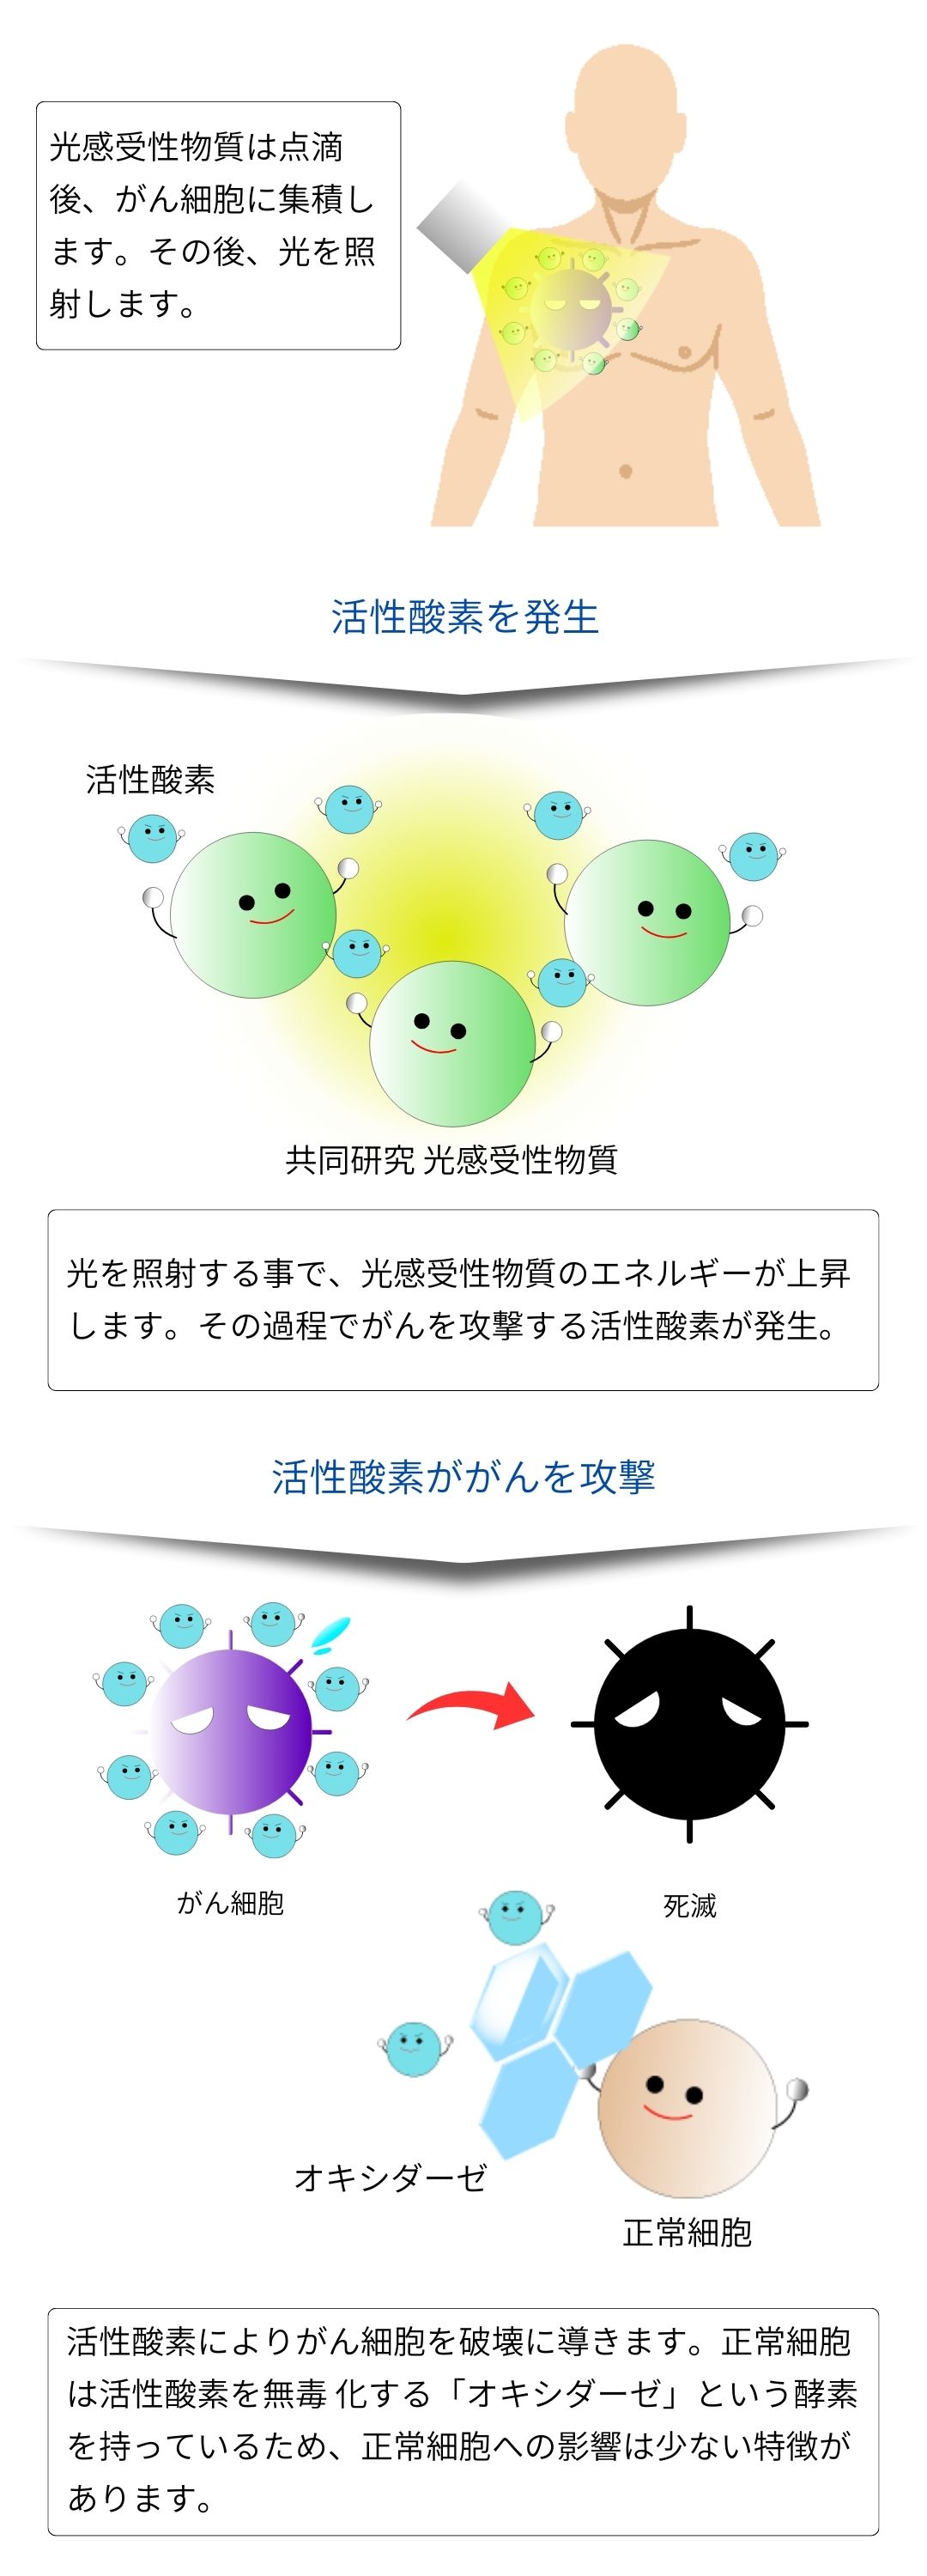

がんの光免疫療法は、光感受性物質という微細な薬剤を点滴で投与した後に、レーザー光をがん細胞へ照射する事によって、光化学反応によりがん細胞をターゲットとして破壊する選択的な治療方法です。

治療の初めの重要なステップとして、患者様には特定の薬剤が点滴によって投与されます。

この薬剤は血管を通じて体内を流れ、ターゲットとなるがん細胞を目指します。

この薬剤は光感受性を持っており、後に行われる光照射治療で重要な役割を果たします。

➁ 薬剤をがん細胞へ集積

正常な血管壁は整然としており緻密に構成されていますが、がん組織の血管壁はこれとは異なり、構造に乱れが見られます。この構造上の差異を利用して、薬剤を効率的にがん細胞に送り届けることができます。この方法は「EPR効果」として知られ、がん治療において重要な役割を果たしています。

➂ 薬剤を保持

薬剤点滴後、保持する事でがん細胞に薬剤が集積します。がん細胞に薬剤が集積するため、がん細胞のみを攻撃する事ができます。これが副作用が少ない理由です。※当日薬剤点滴から照射も可能です。

➃ 体表面照射

特定の波長を有したレーザーを体表面照射することで、がん細胞に集積した薬剤に反応させます。その結果、薬剤は発熱し、がん細胞を攻撃します。体表面照射を数回繰り返す事で、がん細胞を死滅させていきます。

図のように薬剤はレーザー光によって活性化し、活性酸素を生成してがん細胞を破壊します。

光を光感受性物質に当てると、その物質はエネルギーを放出し、この過程で活性酸素が生成されます。

これを「光化学反応」と呼びます。がん細胞は活性酸素に弱く、この活性酸素によって破壊されます。

一方、正常な細胞は活性酸素を無毒化する「オキシダーゼ」という酵素を持っているため、破壊されません。

これも、副作用が少ない理由の一つです。